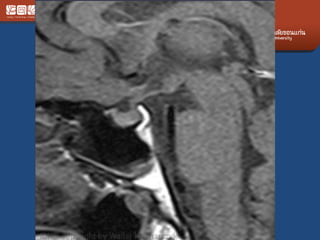

Pituitary Macroadenoma

• Usually soft

• Elevate diaphargma selle

• Often contrasted at diaphargmatic hiatus as

tumor growth into the suprasellar cistern

• Snowman shape

• *commonest large tumor of the skull base